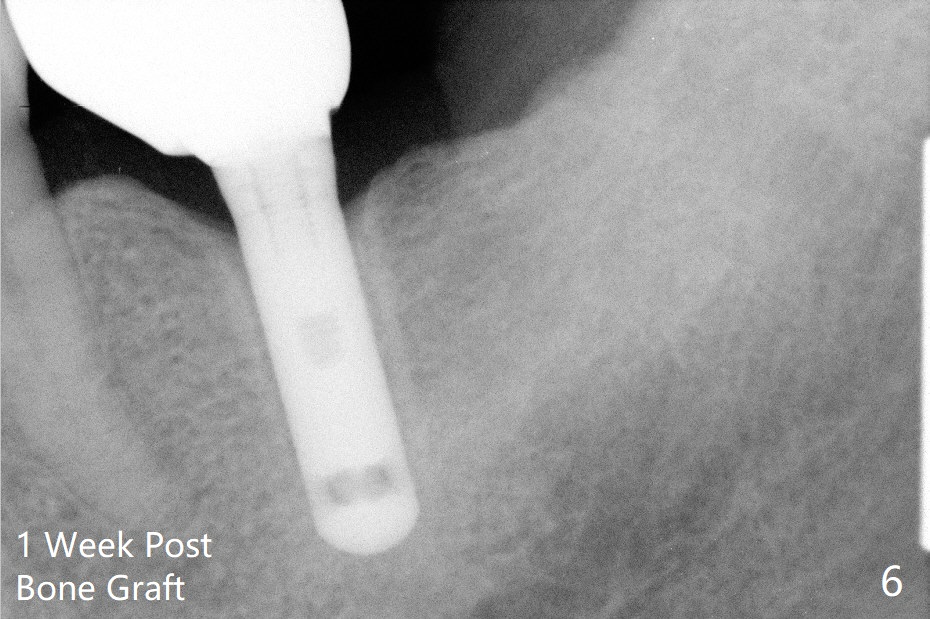

A 69-year-old man needs an implant at #18 (Fig.1,2 CT (sagittal and coronal sections)). In spite of use of surgical stent, the trajectory is not ideal (Fig.3-5). The following day the implant is removed with bone graft (Fig.6). In the 2nd placement, the trajectory is adjusted in each step (Fig.7-9 arrows) with long term stability (Fig.10,11).